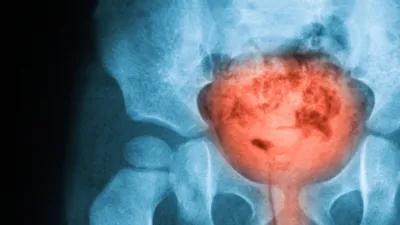

A team at UEA has unveiled research showing nanopore sequencing on a MinION being used to characterise bacteria from urine samples four times more quickly than using traditional methods of culturing bacteria. The research was shown at an international four-day medical conference in San Diego, run jointly by the American Society for Microbiology’s Interscience Conference of Antimicrobial Agents and Chemotherapy (ICAAC) and the International Society of Chemotherapy (ICC).